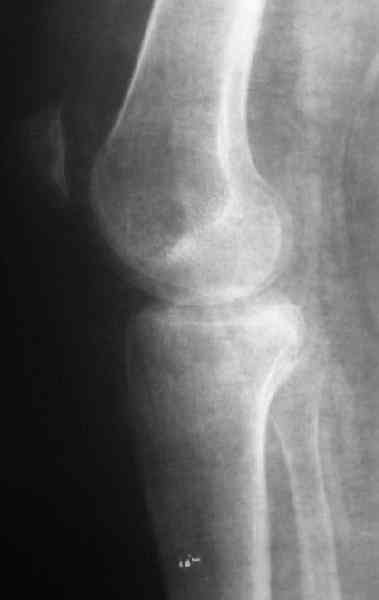

Уважаемый Ростислав. Спасибо что поправили, это у нас по старой привычке, "застарелый" наверное правильно будеть "неправильно вялоконсолидируюшаяся перелом" или есть еще другие варианты, надо подумать.

По тактике лечения, более импонирует второй вариант, но наружная плато расколота и туда при нагрузке внедряется н/мышелка бедра, поэтому после дистракции как репонирвать: или стяжными винтами, или изогнутами спицами или субхондральная костная пластика?